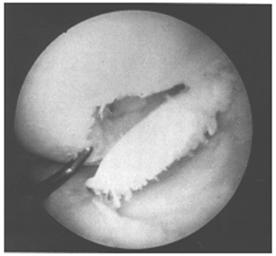

Another classification system has been devised by Bauer and Jackson who identified six types of lesions of the articular cartilage. In their series, they found that rotational forces in direct trauma were the most common causes of injury to the articular cartilage. In most of their cases, the lesions were in the weight-bearing area of the articular cartilage, usually in the medial compartment. The most common associated lesion was a tear of the meniscus. The six types of changes are linear crack, stellate fracture, flap, crater, fibrillation, and degrading (Fig. 29-58). The linear crack is usually split-thickness, and it is often encountered on the lateral tibial plateau in association with ACL injuries. Stellate fracture is usually of a diverging type with central flaking of the cartilage. This is the most common type identified in the series (Fig. 29-59). In a flap tear, the cartilage is avulsed from the subchondral bone (Fig. 29-60). The crater is usually full-thickness and subchondral bone is exposed. Fibrillation is of partial thickness and corresponds to the old Outerbridge classification type III. The final characteristic appearance of abnormal articular cartilage is degenerative and extends down to the subchondral bone.